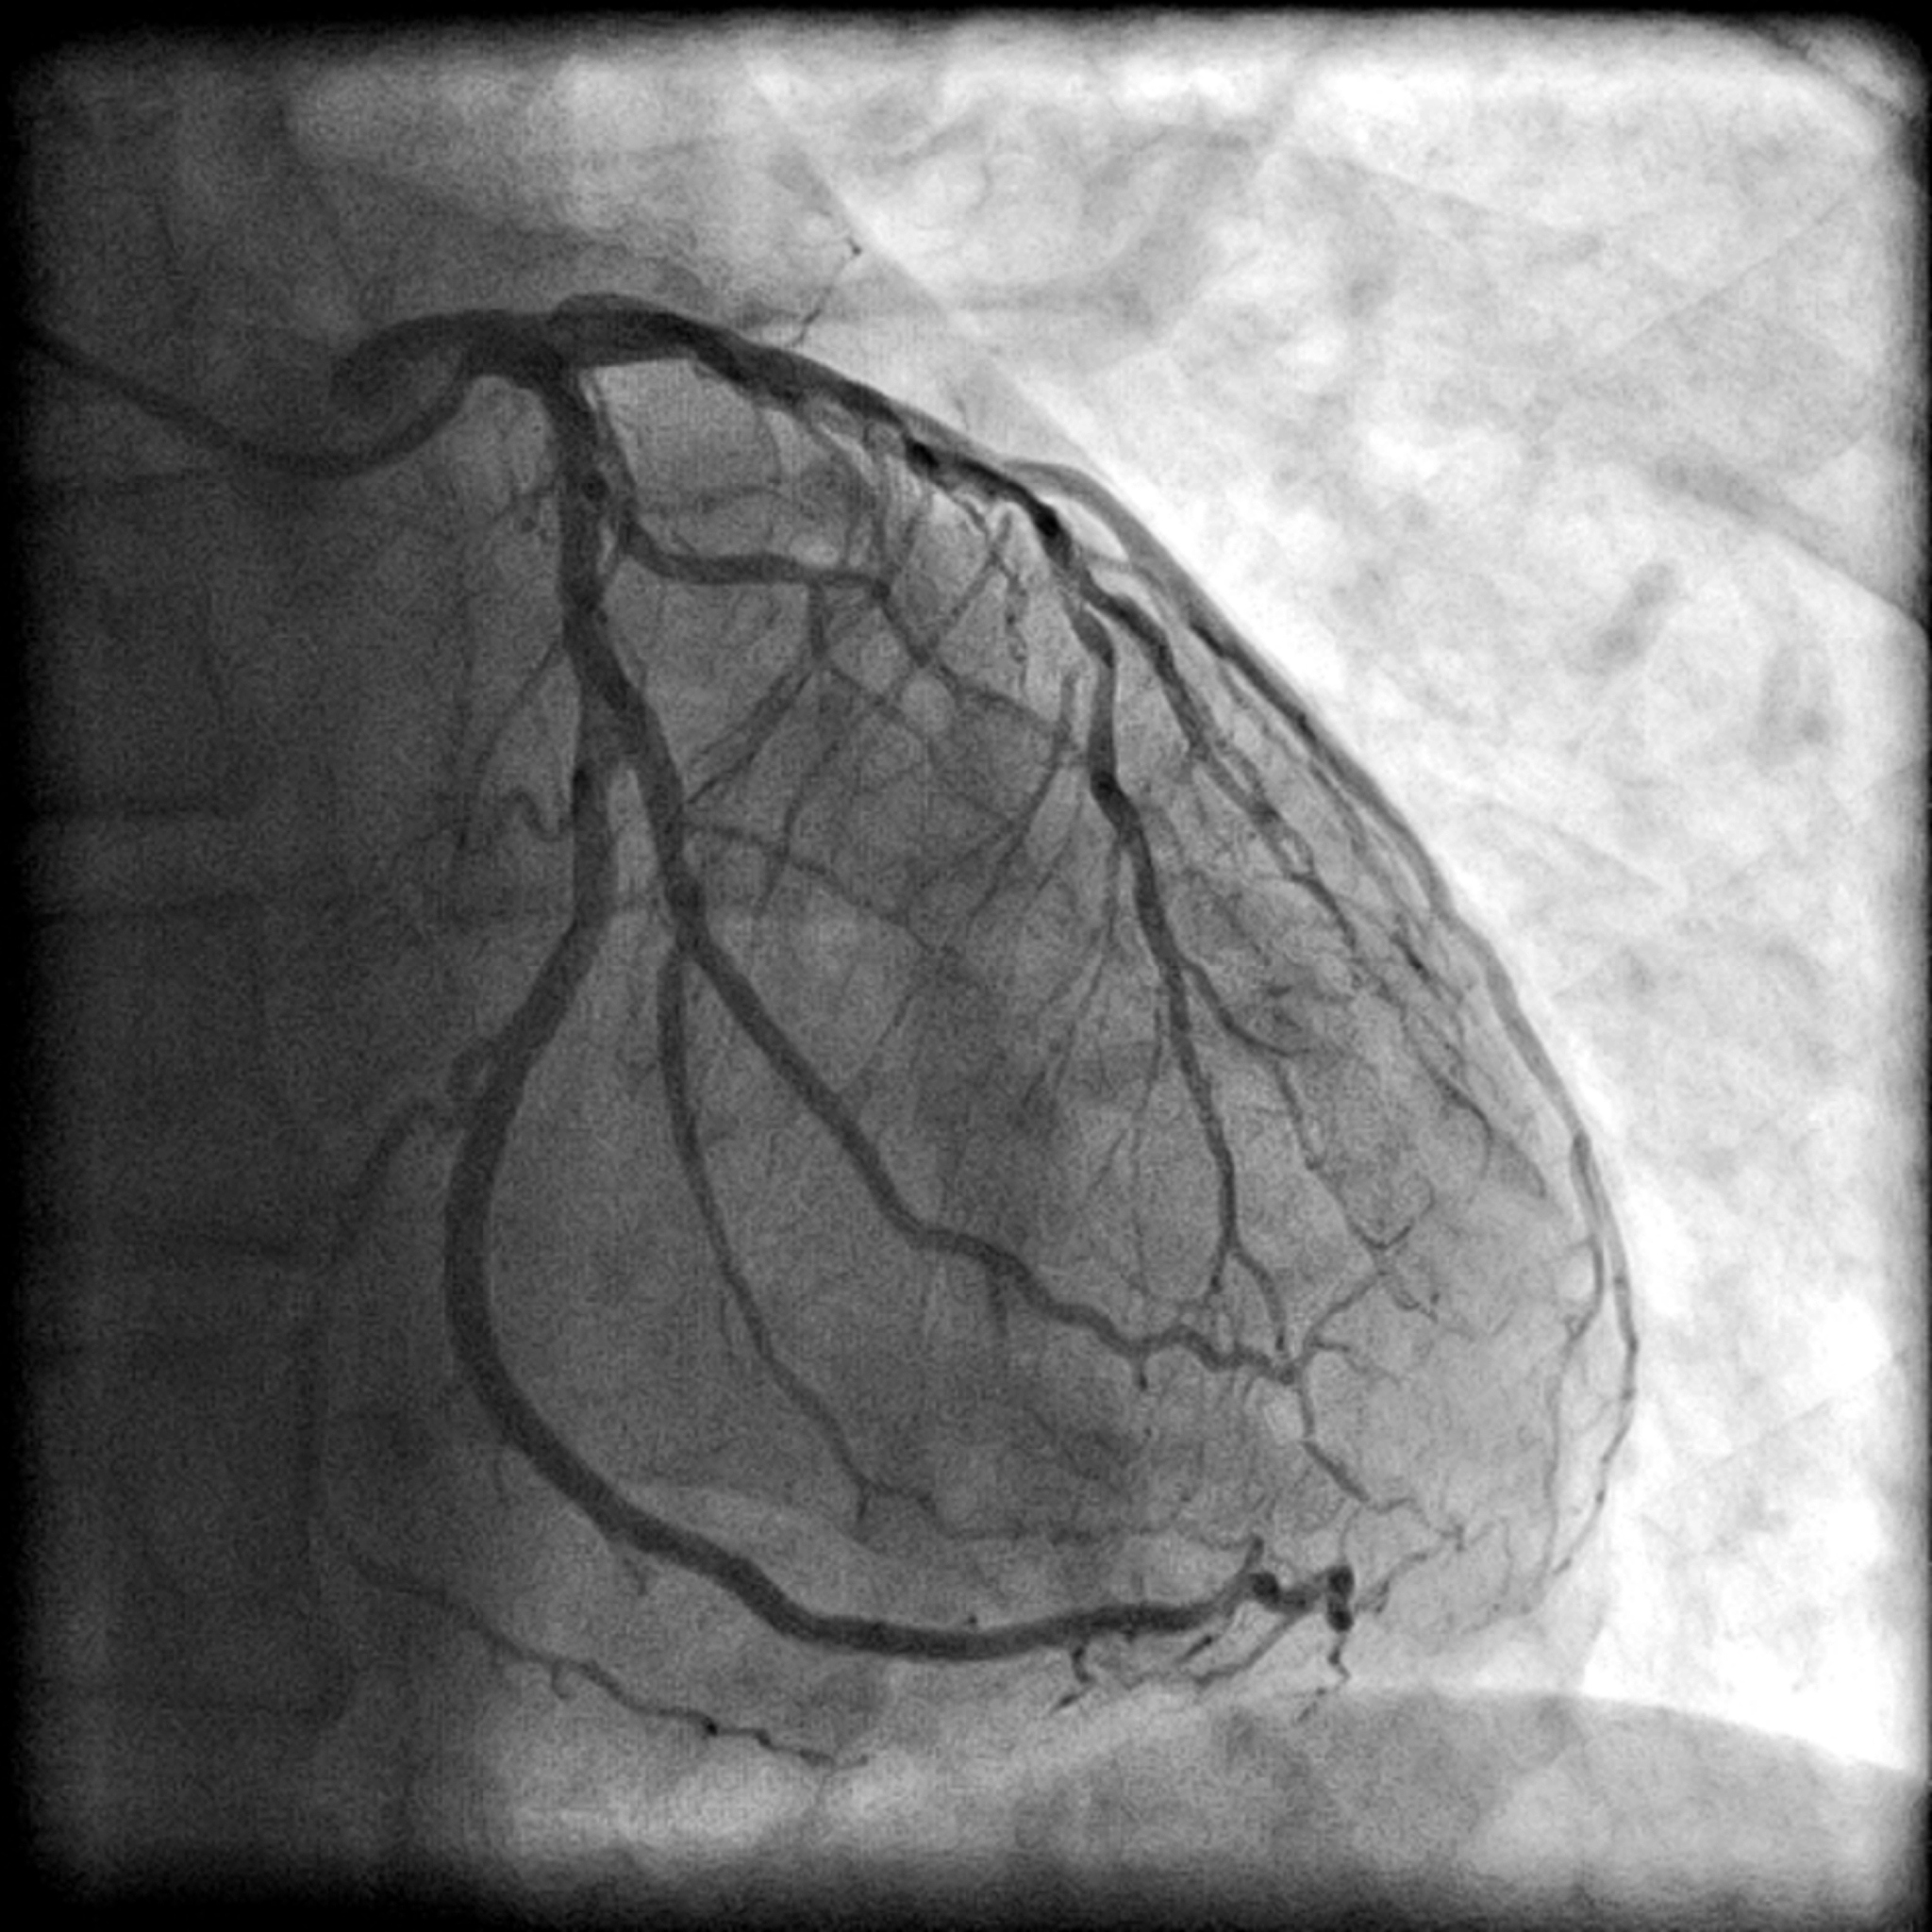

心血管影像报告解读:低回声区域和动脉搏动

此外,我们注意到斑块远端区域存在'低回声'的可疑区域,该区域在动脉搏动时略有振荡。